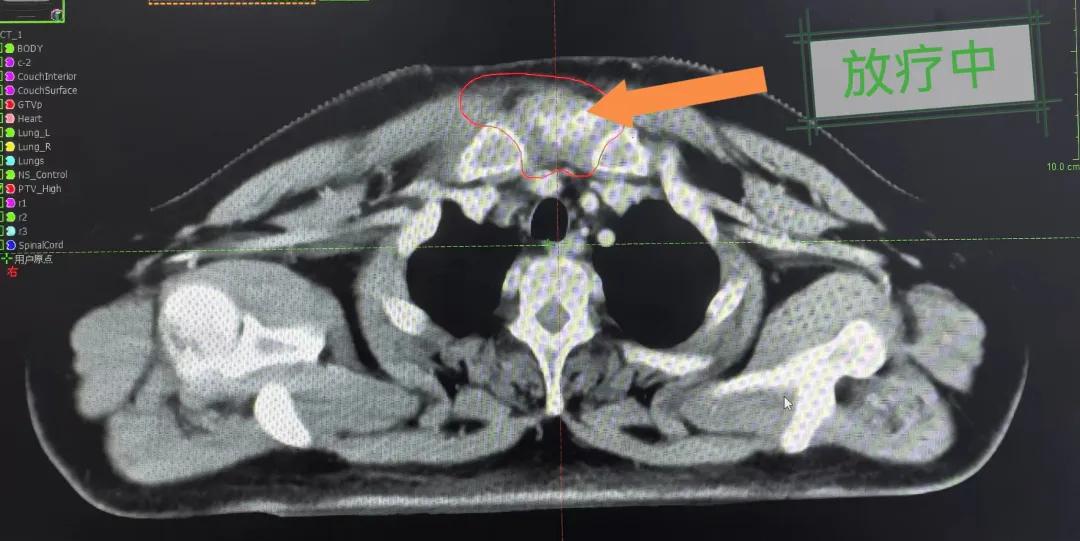

隨后,趙亮主任帶領(lǐng)放療團隊以最快的速度完成了患者的放射治療計劃,在保證放療精準(zhǔn)打擊腫瘤的同時,利用先進的三維立體精確放療技術(shù),最大限度的避免心臟、肺部的損傷發(fā)生,整體治療精準(zhǔn)度達到1mm以內(nèi)。經(jīng)過10次的放射治療后,患者疼痛已明顯減輕,胸部腫物肉眼可見的縮小,患者及家屬臉上終于露出久違的笑臉。

治療期間,患者沒有出現(xiàn)明顯不適,治療結(jié)束后,患者胸壁腫物由最初8cm縮小至約1cm,后患者至外科行手術(shù)治療。